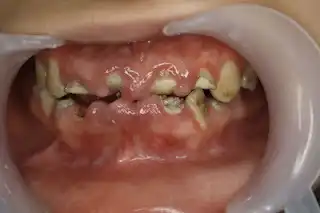

Бегом к стоматологу

Хронический фиброматозный гингивит. Бывает и страшнее

жуть, на цингу похоже